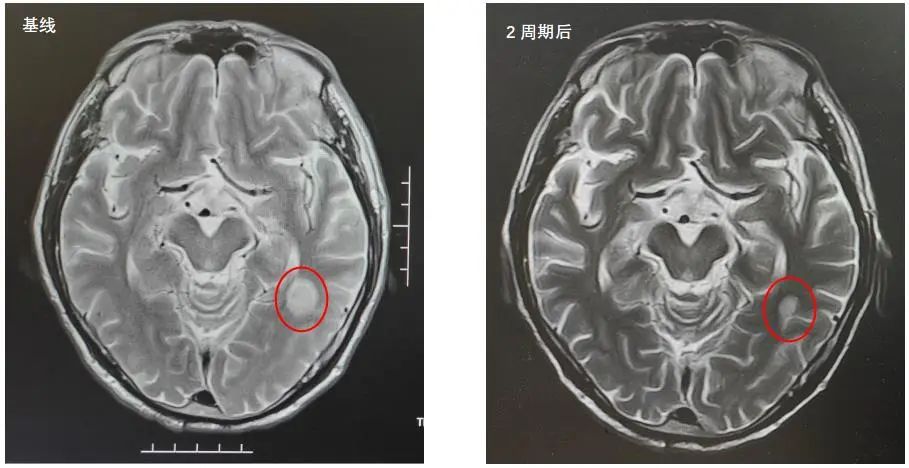

2022年7月5日复查脑部MRI提示:与PACS20220529老片对比,现片示:左侧颞叶强化灶较前稍缩小。

MRI:与PACS20220529老片对比,现片示:左侧颞叶强化灶较前稍缩小。

该患者是一个基线伴有脑转移的广泛期小细胞肺癌患者,《2022年CSCO小细胞肺癌诊疗指南》推荐,对于无症状的脑转移小细胞肺癌患者,一线治疗推荐免疫联合化疗后,再行全脑放疗。此患者在进行4个周期斯鲁利单抗联合卡铂依托泊苷治疗后,影像学提示病灶明显退缩,脑转移病灶也明显缩小,疗效达到PR,充分证明斯鲁利单抗在广泛期小细胞肺癌患者中的良好疗效。